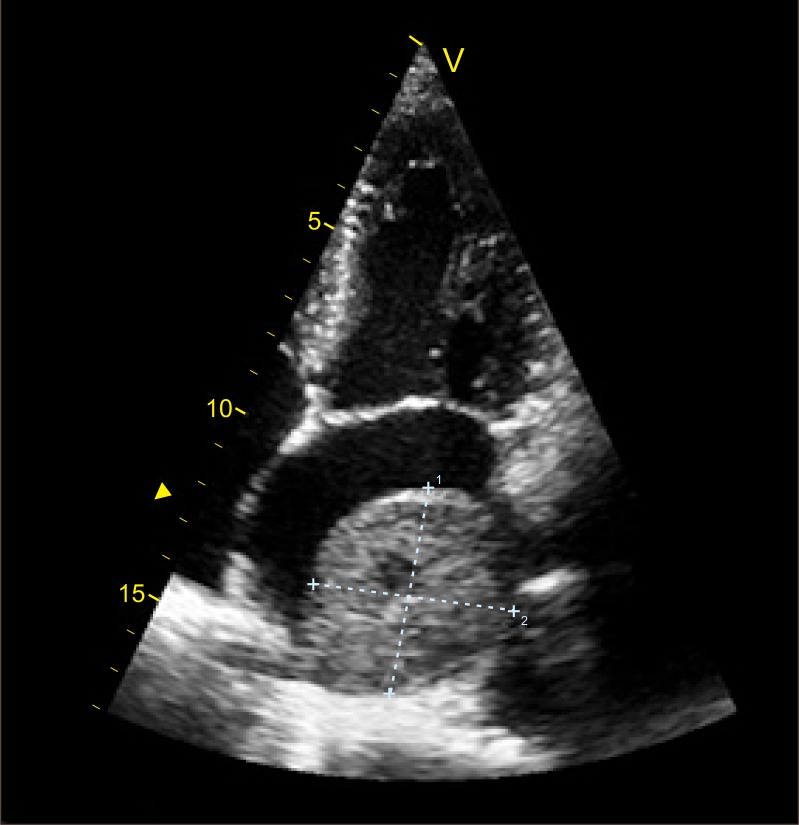

一名39岁男子到首尔大学医院急诊科就诊,主诉胸痛、心悸、头痛。到达后,计算机断层扫描显示7.0 cm×6.2 cm病变,具有副神经节瘤的典型特征。患者在手术前接受了α -受体阻滞剂和β -受体阻滞剂的治疗。我们成功切除了肿瘤,组织病理学结果表明肿瘤确实是副神经节瘤。由于心内副神经节瘤是一种罕见的疾病,我们提出这个病例并进行文献回顾。

A 39-year-old man presented to the department of emergency medicine in Seoul National University Hospital complaining of chest pain, heart palpitation, and headache. Upon arrival, a computed tomography scan showed a 7.0 cm×6.2 cm lesion with the typical features of a paraganglioma. The patient was treated with an alpha-blocker and a beta-blocker prior to surgical intervention. We removed the tumor successfully, and histopathologic findings indicated that the tumor was indeed a paraganglioma. Since intracardiac paraganglioma is a rare disease, we present this case together with a literature review.